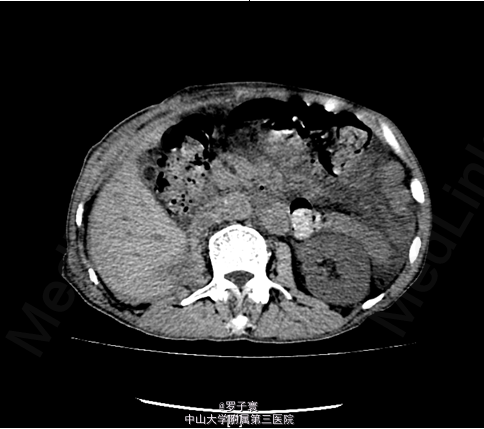

右肾细胞癌并腹膜后淋巴结转移

入院完善相关检查:生化:白蛋白34.8g/L。血常规:血红蛋白浓度111g/L。尿常规:潜血+++,白细胞++,亚硝酸盐阳性(+),白细胞计数1049.20个/ul,红细胞计数167.80个/ul。凝血功能、术前筛查、PSA、AFP、CEA、胸片、心电图未见明显异常。双肾CTU,考虑右肾肾癌并淋巴结转移可能性大,彩超腹部大血管提示:腹膜后多发肿大淋巴结,考虑为淋巴结转移Ca可能性大。核素肾动静态显像:1、右肾灌注、功能中度降低;2、左肾灌注,功能正常。

排除手术禁忌症后患者于2015-4-26在全麻下行右侧肾癌根治性切除+腹膜后淋巴结清扫术,术程顺利,术后病理示:右肾细胞癌并腹膜后淋巴结转移。患者术后手术切口愈合不良,遂于2015-5-19行腹部伤口清创缝合术,术程顺利,术后恢复良好。